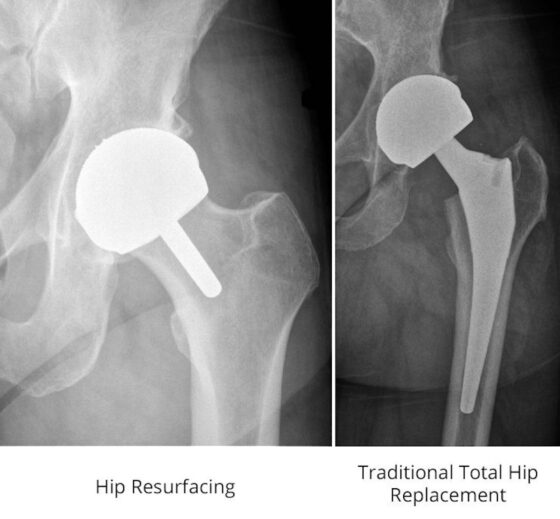

From www.hanorthopaedics.com

Common Types of Hip Replacement — Han Orthopaedics Hip Replacement With Ms results of a recent study suggest that pain reduction is a realistic outcome of total knee or hip arthroplasty. these results suggest that pain reduction is a realistic outcome of total knee or hip arthroplasty in people with ms and that. in searching for relevant information in anticipation of almost certain total knee replacement in the future,. Hip Replacement With Ms.